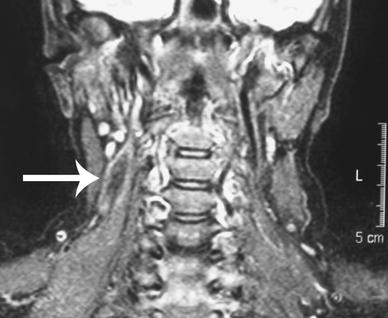

Ultrasound scanning showed a hyperechoic mass within the pre-vertebral muscles of the posterior triangle of the neck and fine needle aspiration failed to yield sufficient aspirate for cytopathological analysis. A computerised tomography scan revealed a soft tissue mass arising laterally to the origin of the deltoid muscle, suggestive of a soft tissue sarcoma. Magnetic resonance imaging (MRI) of the neck showed a 3 × 2 × 1 cm3 lesion of intermediate T1 and low T2 signal intensity within the right posterior cervical space, that could not be separated from the adjacent scalene and levator scapulae muscles. There was no evidence of cervical spondylosis. A peripheral area of enhancement surrounded the lesion, suggesting a neoplastic or inflammatory process (Fig. 2). An incisional biopsy was recommended by the multidisciplinary head and neck oncology team and the histological analysis confirmed the diagnosis of collagenous fibroma.

Fig. 2

T2-weighted MRI scan of neck (coronal view). The tumour (arrow) is shown in the right cervical space as an area of low signal intensity with a surrounding region of peripheral enhancement

MRI remains the preferred imaging modality at present to delineate collagenous fibromas, which have low signal intensity on T2-weighted scans ascribed to the low cellularity of these lesions. However, a finding of low T2 signal intensity of a soft tissue tumour on MRI is not unique to collagenous fibromas, and important differential diagnoses cannot be excluded on the basis of this finding. These include neurofibroma, cicatricial fibroma, malignant fibrous histiocytoma, aggressive fibromatosis, calcified masses and soft tissue malignant sarcomas [4].